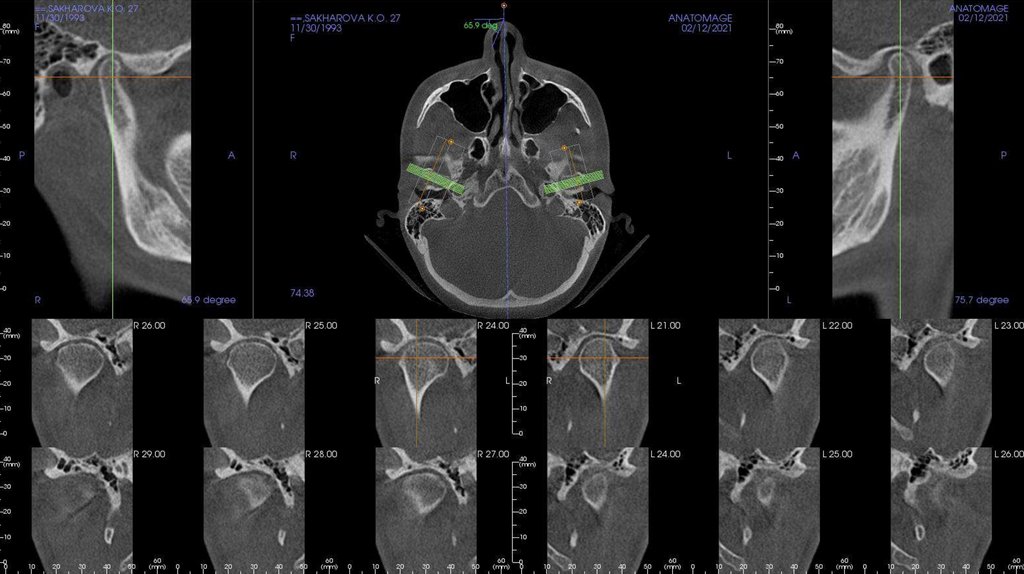

По рассчетам снимков:

• Ретрузия резцов верхней челюсти

• Компрессия головок суставов, особенно правого( началось

ремоделирование)

• Костная ассиметрия(10 мм)

• 2 класс

• 25, 46 зуб – нуждается в санации

• Требуется профессиональняа гигиена полости рта

• Клиновидные дефекты 43, 44

• 18, 28, 38, 48 отсутствуют.